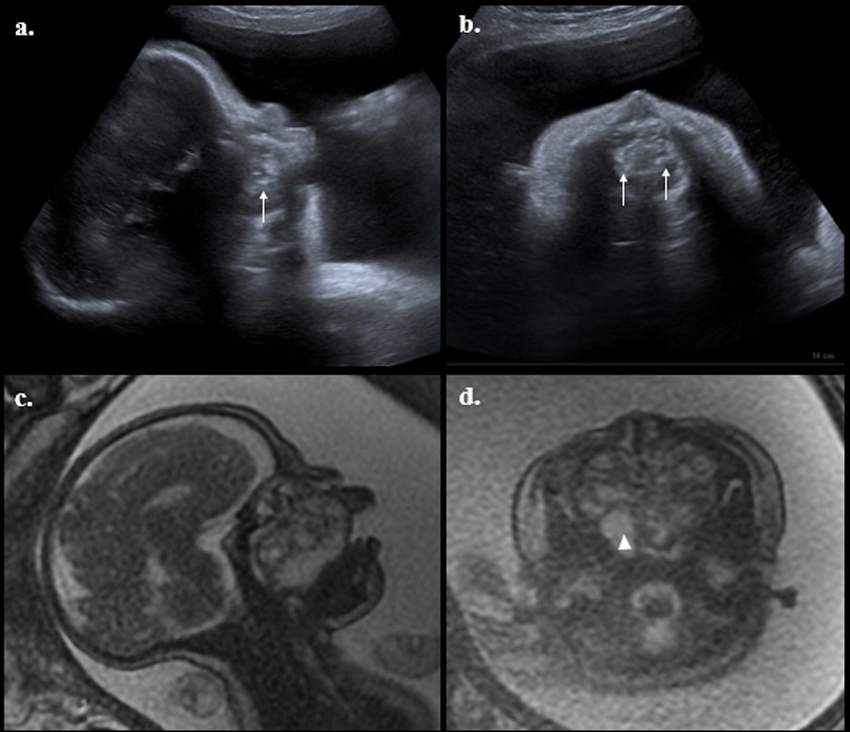

Con diagnóstico de amenaza de parto pretérmino asociado a posible polihidramnios, se hospitalizó para manejo con cristaloides, tocólisis con nifedipino, administración de corticoesteroides para maduración pulmonar fetal y se solicitaron estudios complementarios para evaluar bienestar fetal y descartar posibles etiologías que explicaran el polihidramnios. La ecografía obstétrica reportó biometría concordante para 33 semanas y 5 días, peso estimado fetal de 2.170 g en percentil 50 %, placenta corporal posterior grado II e índice de líquido amniótico de 47 cm. Como hallazgo positivo a la exploración ecográfica se evidenció perfil fetal con apertura bucal persistente y presencia de imagen dependiente del paladar duro, de contornos irregulares, ecogenicidad mixta con calcificaciones en su interior que ocupaba la cavidad bucal fetal con diámetros de 37 x 37 x 38 mm para un volumen de 28 cm3 (Figura 1). Ante el hallazgo ecográfico se sospechó teratoma nasofaríngeo, por lo que se completó estudio ecográfico con neurosonografía y ecocardiograma fetal, los cuales fueron normales. En cuanto a los laboratorios maternos, el hemograma reportó: leucocitos, 11.780 células//xl; neutrófilos, 65 %; hemoglobina, 12,1 g/dl; hematocrito, 35 %; plaquetas, 203.000 plaquetas/µl; proteína C reactiva (PCR) negativa, urocultivo negativo, cultivo recto-vaginal para estreptococo del grupo B negativo y prueba de citomegalovirus IgG positiva e IgM negativa.

Por persistencia de actividad uterina asociada a dificultad respiratoria secundaria a distensión abdominal, se realizó amniodrenaje de 1.500 cc de líquido amniótico claro, sin complicaciones, y se obtuvo cariotipo fetal euploide 46, XX. Se completó el estudio de la anatomía fetal por resonancia magnética, secuencias ponderadas en T2 corte sagital y axial, documentando la existencia de una lesión con bordes lobulados, expansiva, que ocupaba la nasofaringe y orofaringe, de componente predominantemente sólido por la presencia de zonas hiperintensas, con un tamaño de 37 x 47 mm, sin estigmas de compromiso de las órbitas o de sistema nervioso central (Figura 1). Durante la evolución la paciente presentó ruptura espontánea de membranas, por lo que se indicó terminación de la gestación por cesárea bajo protocolo de EXIT (7). Se obtuvo recién nacido de sexo femenino, de 2.180 g, Apgar 5, 8 y 9. Durante la adaptación neonatal y bajo intubación orotraqueal la recién nacida presentó bradicardia (60 latidos min) y ausencia de esfuerzo respiratorio, por lo que requirió reanimación neonatal con adrenalina y solución salina por vía umbilical acompañada de masaje cardiaco, con retorno de la circulación espontánea.

Una masa sólida heterogénea de 39 x 50 milímetros, con calcificaciones internas y algunas regiones intratumorales de comportamiento graso, con epicentro en la cavidad nasal, de aspecto expansivo que remodela la cavidad nasal y celdillas etmoidales, que invade y remodela la cavidad oral, reduce en la profundidad de las órbitas generando hipertelorismo y leve grado de proptosis ocular. (Figura 3).